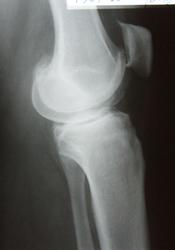

суставная щель неровномерно сужена только с одной стороны.заострение и вытягивание межмыщелкового возвыщение.подхрящевая костная пластинка уплотнена.костные разрастание по краям суставной поверности.

Краевые костные разрастания и субхондральный остеосклероз всегда являются косвенными признаками функциональной несостоятельности

суставных хрящей.

Обязательными признаками деформирующего артроза являются сужение суставной

щели, краевые костные разрастания, субхондральный остеосклероз. Второй и третий признаки (краевые костные разрастания и субхондральный остеосклероз) могут широко варьировать, но без первого признака (сужение суставной щели) деформирующего

артроза не бывает. Не всякая деформация суставных концов является деформирую- щим артрозом.

ВЫВОДЫ.

В результате проведенного рентгенологического исследования сустава выявлены:

1. Признаки прямо указывающие на дегенерацию суставного хряща:

- сужение рентгеновской суставной щели соответствует объемному уменьшению суставного хряща;

- субхондральный остеосклероз, как ответная реакция костной ткани на увеличение механической нагрузки в суставе;

- остеофиты на краях суставных поверхностей, как ответная реакция костной ткани на увеличение механической нагрузки в суставе.

Диагностическое заключение.

Деформирующий артроз сустава стадии по трёхстепенной классификации по Н.С. Коссинской; стадии по классификации Kellgren и Lawrence.